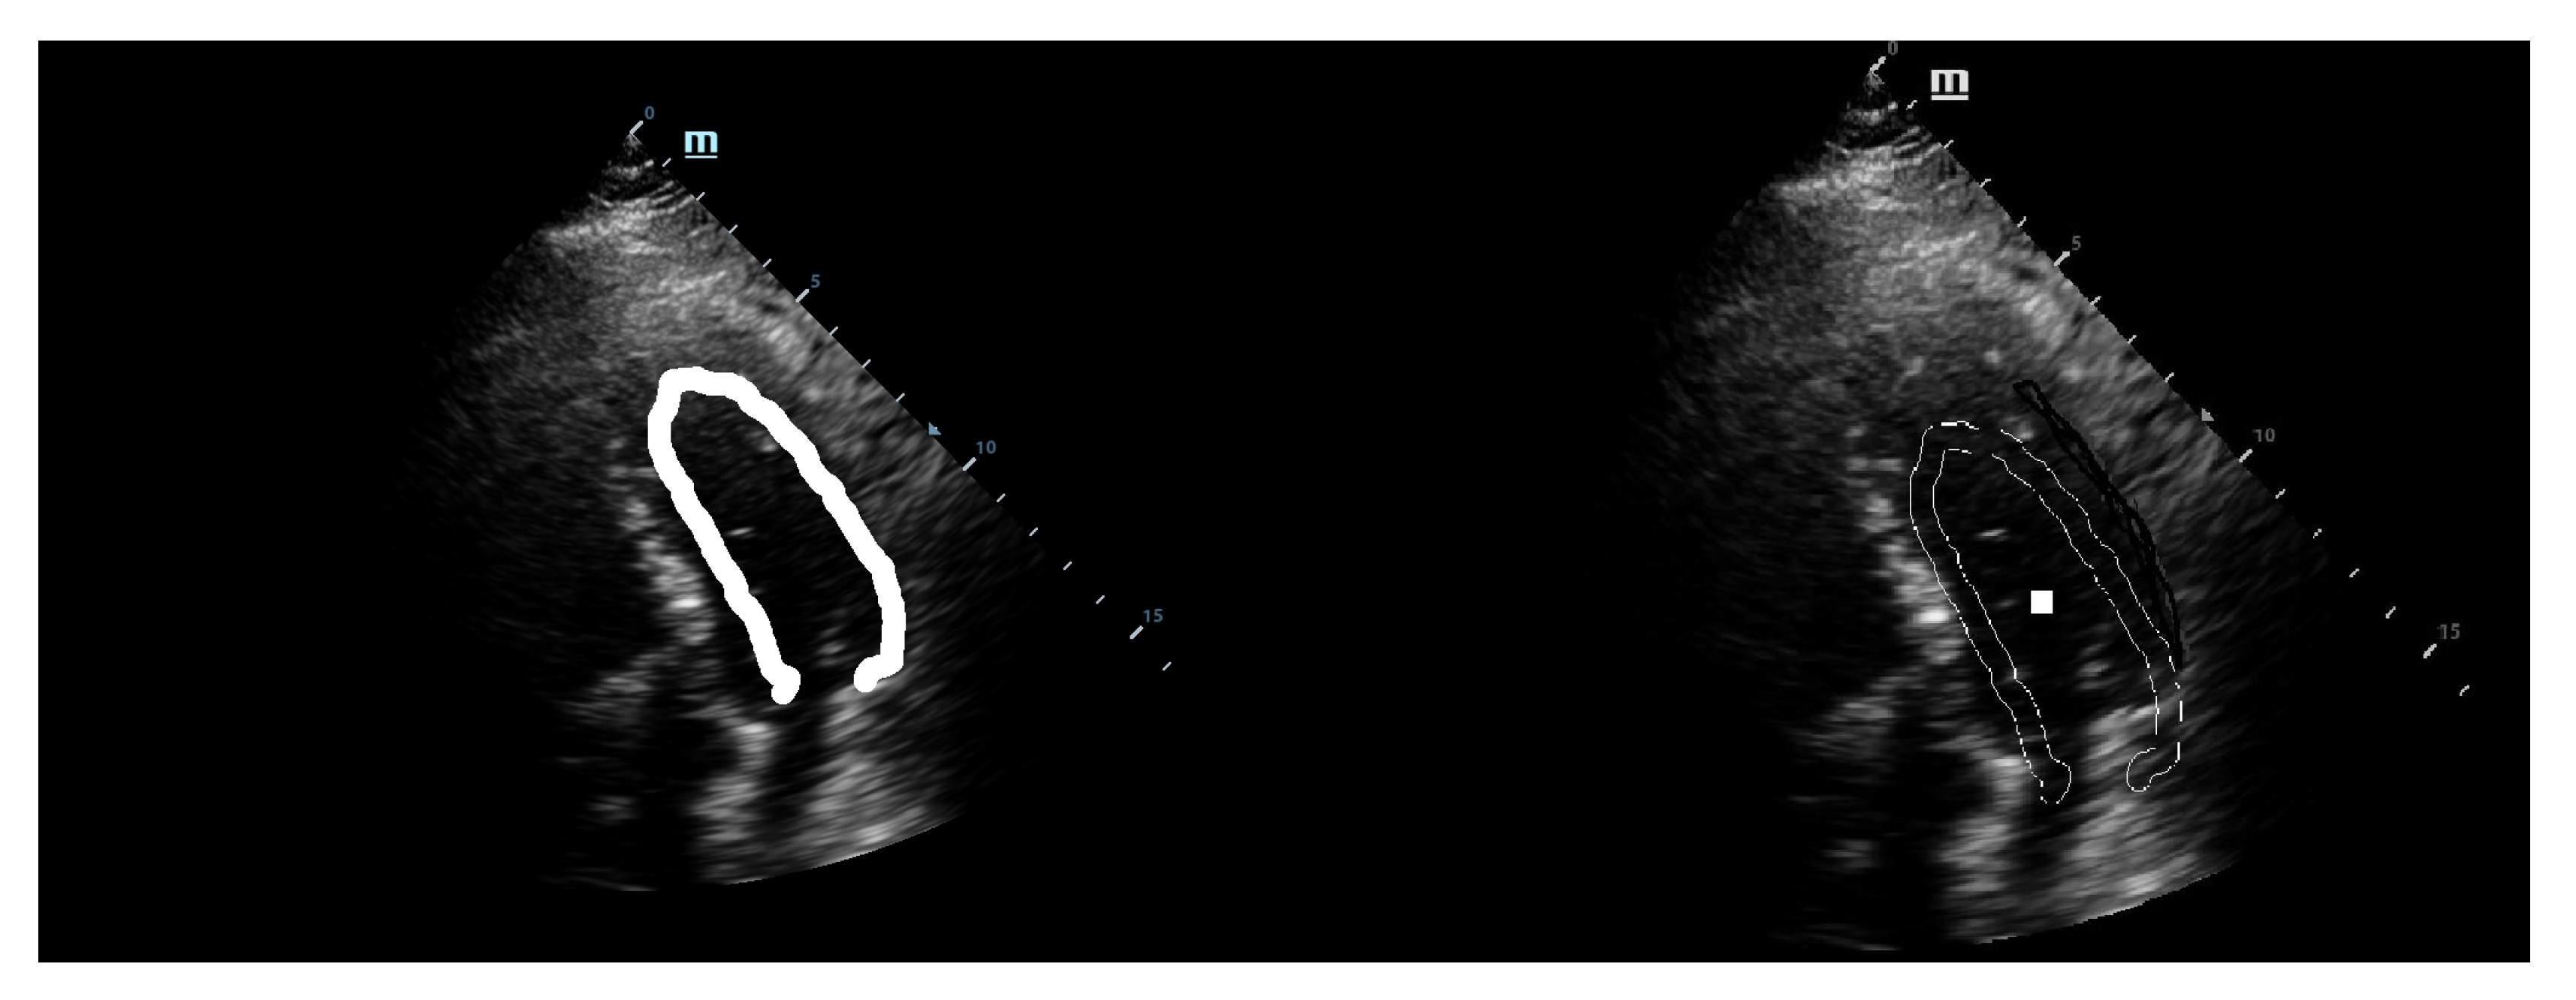

The first step was a preliminary tracing of the endocardium (very rough drawing) on an ultrasound image done by hand by a trained cardiologist. That was the beginning of our approach. From this initial sketch (drawing), we extracted a draft template (see Figure 1).

This template was used for the initial tests with our implementation of the GHT. We considered an anisotropic Hough transform to allow deformations of the template that could best fit the left ventricular wall. By directly applying the GHT with this template on an echocardiographic image, we obtained a rough marking of the left ventricular wall. The results are shown in Figure 2.

Figure 1. Initial drawing and template extraction.

Figure 2. Direct application of the anisotropic Hough transform.